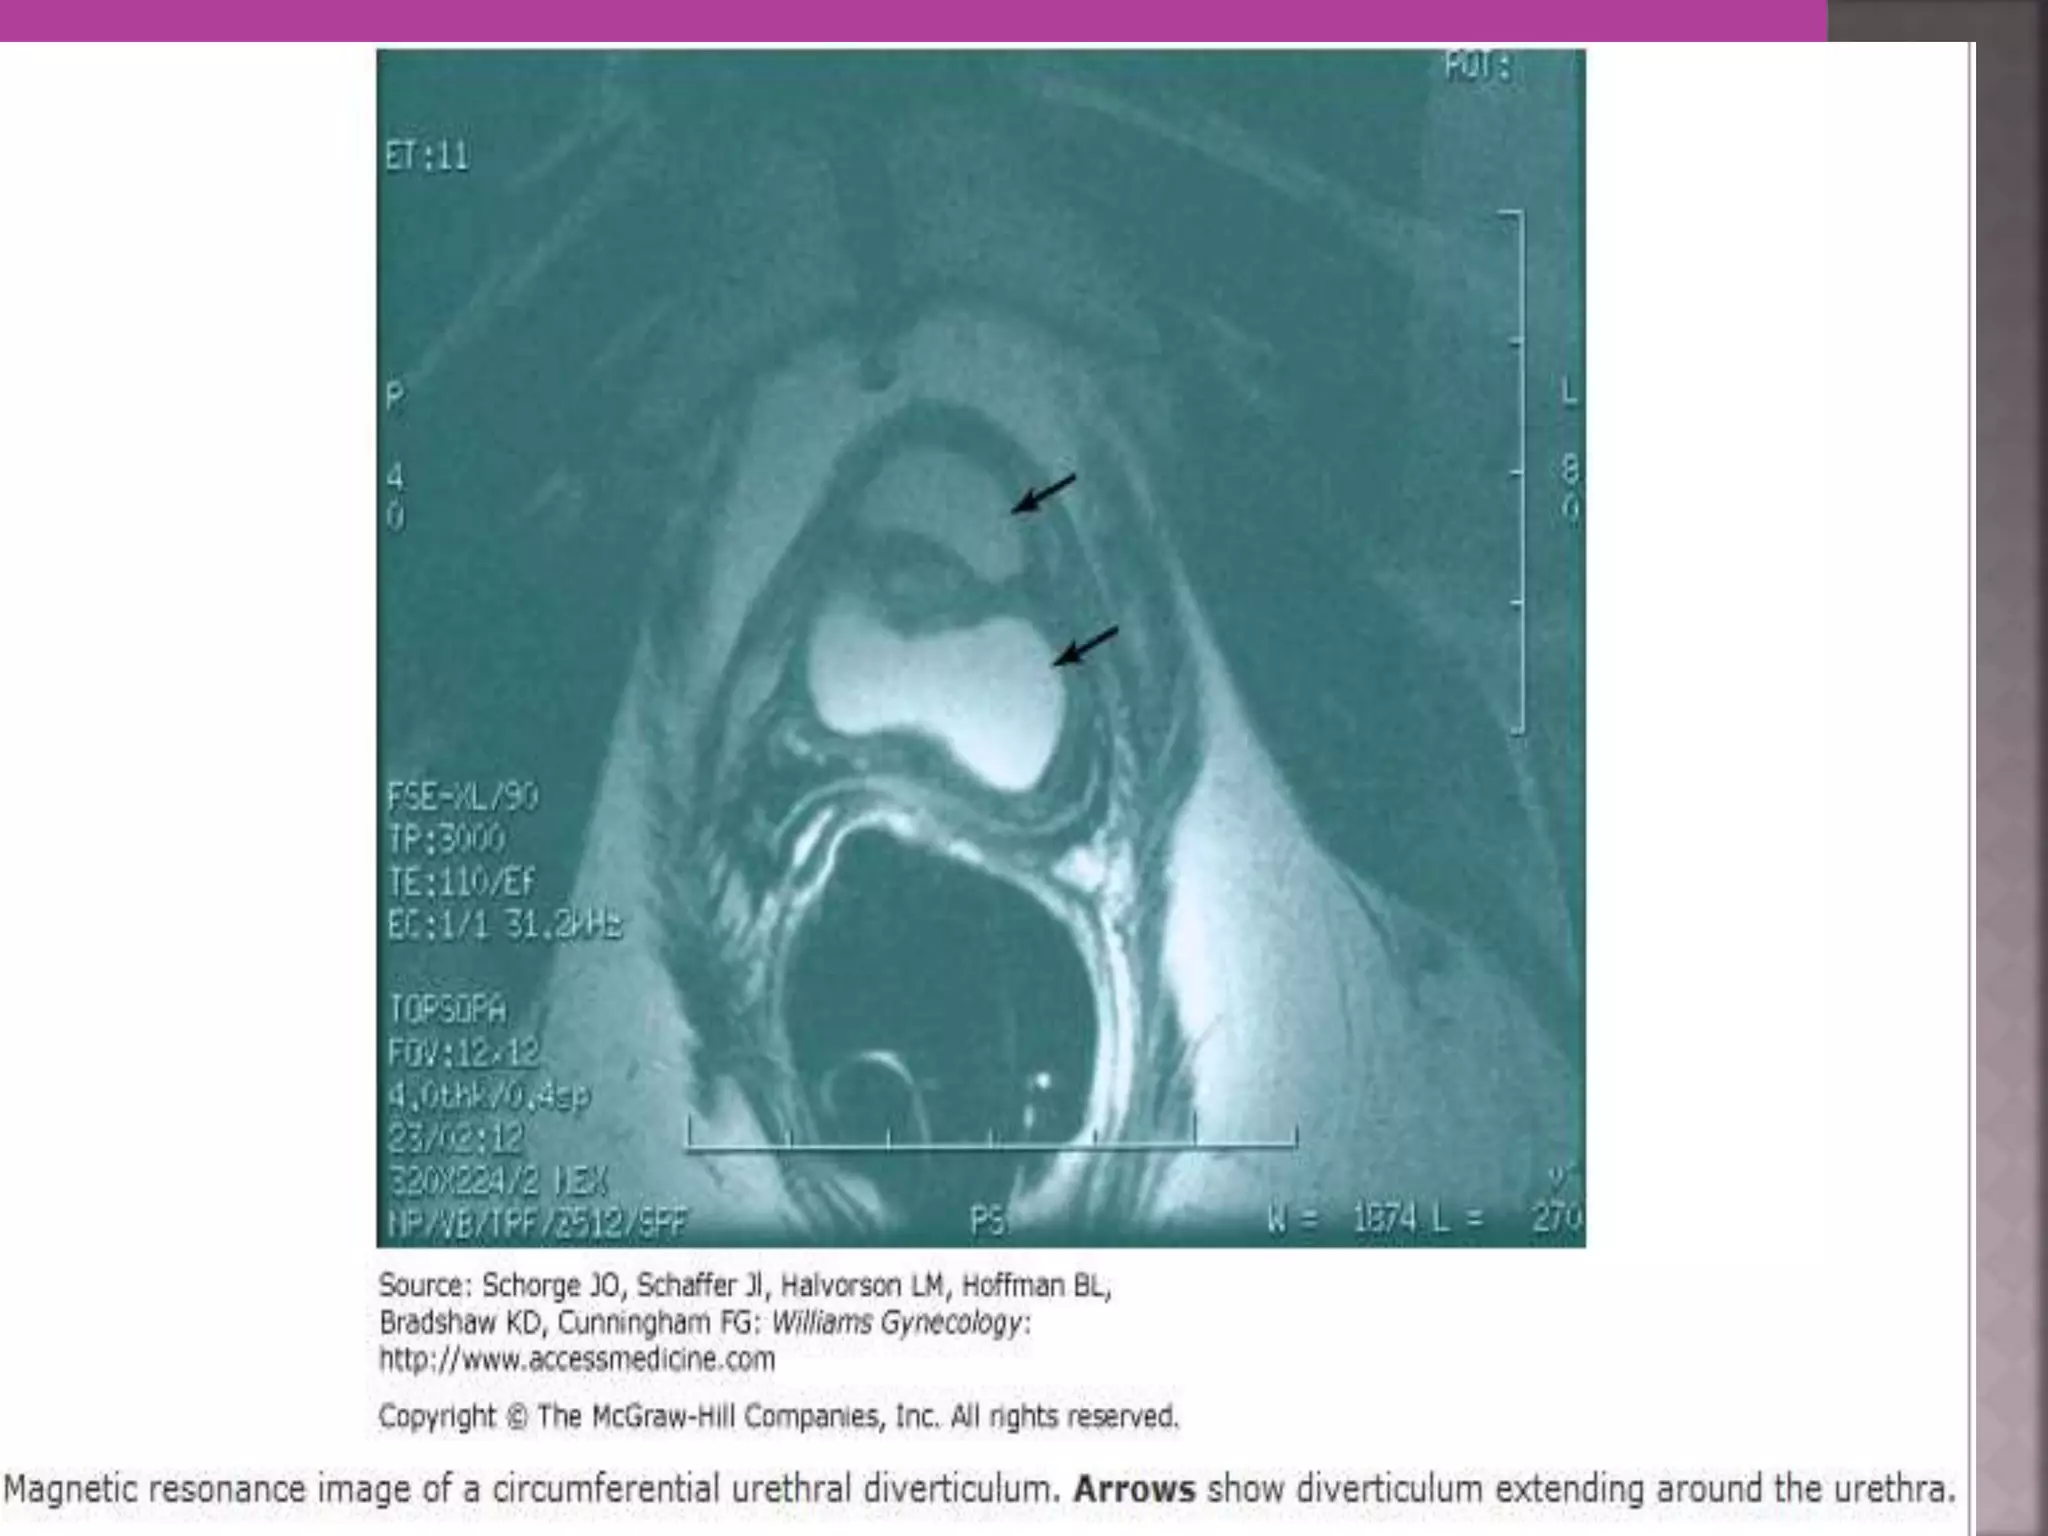

 Study ofnormal uterus and adnexa – with aim to have clear image of normal myometrium, endometrium , ovary and follicles within the ovary.  Myoma—to differentiate myoma from adenomyoma.localization of myoma—sub serous/ intra mural or sub mucous.  Adenomyosis---accurate diagnosis.  Congenital uterovaginal anomalies— bicornuate, septate,subseptate , unicornuate, didelphys ,rudimentary horn and vaginal atrasia etc